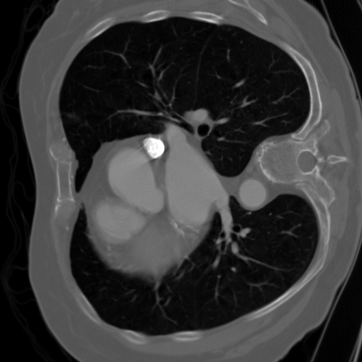

For the CTreconstruction experiments, we consider the LoDoPaB-CT dataset [89]. Its ground truth images of size 362×362362\times 362 are based on reconstructions in the LIDC/IDRI database [13]. While the original dataset is very large, we use the 35223522 images from the validation set for training, and the 128128 images from the first test batch for testing.